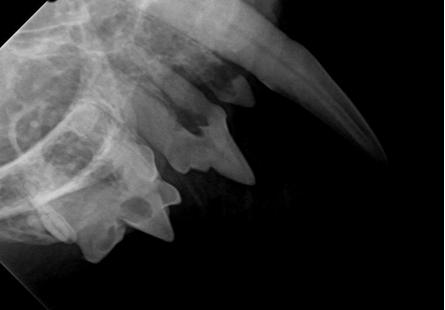

• Dentale röntgen bij uw huisdier

Onze kliniek is uitgerust met moderne digitale röntgenapparatuur speciaal voor het gebit van uw huisdier. Op deze manier kunnen wij op een snelle en efficiente manier, de tand en zijn wortel beoordelen en hierdoor een beslissing nemen of bijvoorbeeld de tand wel of niet getrokken moet worden. Ook de toestand van de kaak kan mooi in beeld gebracht worden (denk hierbij aan fracturen of tumoren). Dit onderzoek kan alleen onder algehele narcose uitgevoerd worden.